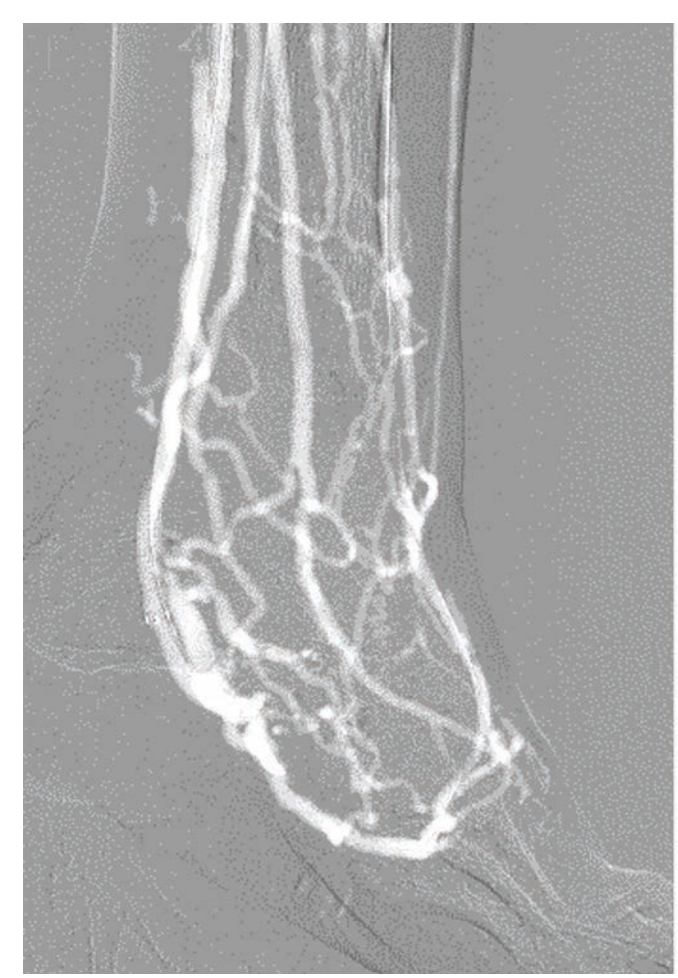

Valvulotomy in the LPV was performed with a 4- x 120-mm UltraScore scoring balloon (BD). A 5- x 250-mm Viabahn covered stent (Gore) was placed across the fistula and down the PTV to the LPV. The Viabahn covered stent in the PTV was post-dilated with a 5- x 100-mm Ultraverse balloon, and the short segment in the PTA was post-dilated with a 4- x 40-mm Ultraverse balloon. The final angiography was performed with CO2 showing excellent blood flow to the foot (Figure 4). Hemostasis of the LPV access was achieved with a combination of an intravascular balloon endoclamp and external manual compression. Hemostasis of the left CFA was achieved with a Perclose Proglide closure device (Abbott).

The patient was discharged without a change from his baseline creatinine of 2.0 mg/dL. As is our institution’s protocol, we discharged the patient on atorvastatin and a 1-month regimen of aspirin, clopidogrel, and rivaroxaban with planned subsequent de-escalation to only aspirin and rivaroxaban for prophylaxis of in-stent venous thrombosis. He followed up weekly in our wound care clinic for several minor debridements and eventually had a TMA 2 months later (Figure 5). His tissue oximetry improved from 18 to 56 mm Hg. His wound healed 9 months after the pDVA procedure, and he was in remission 2 years after the index procedure.

This case report describes a patient classified as no-option CLTI based on the following factors: This patient did not have any autologous venous conduits for surgical bypass. Foot X-ray revealed moderate-to-severe calcification with a MAC score of 4. He had W2-I2-fI1, indicative of a high amputation risk without revascularization. On CO2 contrast angiography, there was a segment of a patent proximal DP, but without evidence of distal branches or microvasculature that are needed to theoretically perfuse the forefoot and heal a TMA. Therefore, together with a history of prior failed revascularization attempts and severe small artery disease, the decision was made to defer another attempt at retrograde revascularization and instead pursue pDVA.